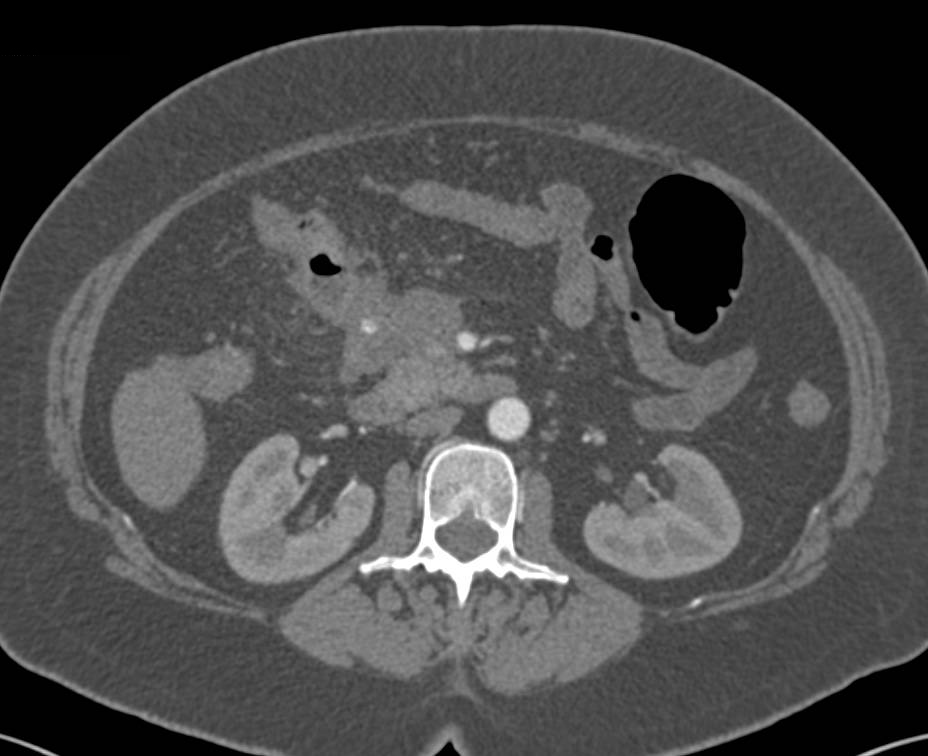

Scleroderma with Dilated Small Bowel